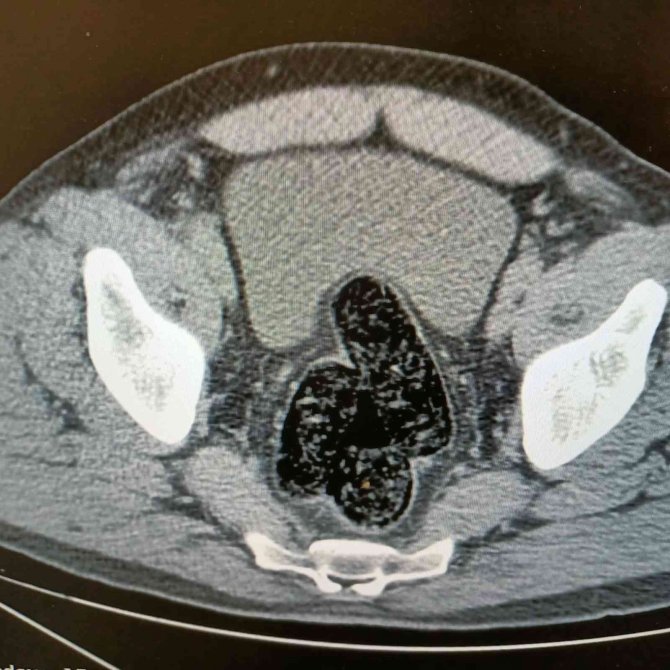

Ağrı'da, uyuşturucu veya uyarıcı madde ticareti yapan veya sağlayan kişilere yönelik yapılan çalışmalar neticesinde Bölge Trafik Uygulama Noktası'nda durdurulan 04 T 3052 plakalı araçta yolculuk eden İran uyruklu bir kişide arama yapıldı. Yapılan aramalar sonucunda, şahsın pantolonunun cep kısmında iki parça halinde şeffaf poşete sarılı vaziyette 10.17 gram gelen metamfetamin maddesi ele geçirildi. Şahsın devam eden işlemlerinde gözlerindeki kızarıklık, yemek ihtiyacı istememesi, aşırı tedirgin davranışlar sergilemesi üzerine yapılan iç beden muayenesi neticesinde röntgen vasıtasıyla makat ve bağırsak kısmında uyuşturucu kapsülleri olduğu tespit edildi. Doğal yöntemlerle şahıstan 12 adet kapsül toplam daralı ağırlığı 345.19 gram gelen metamfetamin ele geçirildi. Şahsın üzerinden ve iç bedeninden toplamda 355.36 gram uyuşturucu madde ele geçirildi.